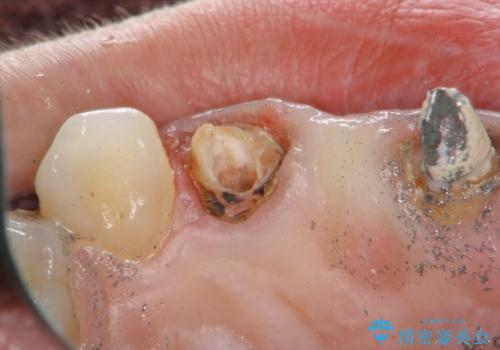

- 前歯のブリッジがすぐに外れる、歯ぐきが腫れている、見た目を良くしたい、と希望され来院されました。

現在装着されているブリッジを除去したところ、歯ぐきよりも上に存在する歯質(縁上歯質)が少なく、土台の形態の悪さや不適合などさまざまな問題があります。